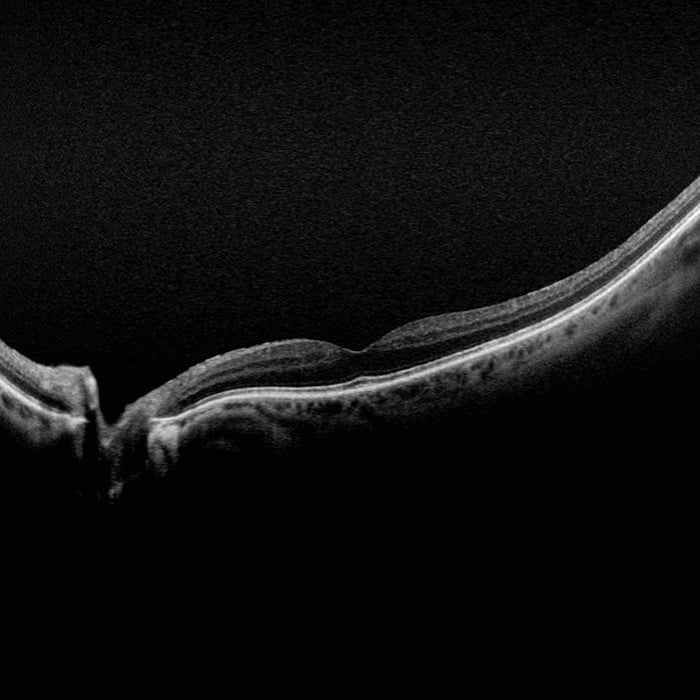

MonacoPro bietet Ihnen faszinierende neue Möglichkeiten, Ihre klinischen Untersuchungen zu vervollkommnen. Als einzige Ultra-Weitwinkel- Bildgebung der Netzhaut mit integriertem SD-OCT liefert Ihnen MonacoPro ein 200° optomap-Bild in weniger als ½ Sekunde und erstellt zudem 40°-OCT-Querschnittsaufnahmen von Netzhautstrukturen. MonacoPro ermöglicht eine schnelle multimodale Bilderfassung mit Farb-, Autofluoreszenz- und OCT-Scans für beide Augen in nur zwei Minuten.

• OCT des zentralen Pols ermöglicht eine umfassende multimodale Bildgebung

• optomap-Bilder und OCT-Scans werden korreliert, um die Befundung zu erleichtern

| Tomographische Bildgebung |

Signaltyp: Optische Streuung vom Gewebe |

| OCT Charakteristika |

Spektral-Domänen OCT |

| OCT Scan Typen |

Linien Scan |